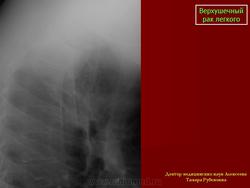

Верхушечный рак легкого

Рентгенологическую симптоматику опухолевого поражения верхушечного сегмента легкого в виде “апикального колпака” с развитием клинического синдрома, обусловленного сдавлением или прорастанием плечевого сплетения, сопровождающегося интенсивными, постоянными болями в верхней конечности и лопатке, впервые описал Pancoast H. (1924г., 1932г.).

Рентгенологические проявления верхушечного рака легкого обусловлены стадийностью его роста, при которой можно выделить 2 группы.

Первая группа: верхушечный рак без синдрома Панкоста - опухоль не выходит за пределы легочной ткани. Опухолевые узлы округлой или неправильной формы, различных размеров, однородной структуры с бугристой поверхностью и нечеткими контурами, которые в виде тяжей распространяются в прилежащие отделы легочной ткани.Может выявляться неоднородная дорожка к корню легкого в результате перибронхиального роста опухоли в сторону корня, при этом отмечается неравномерное сужение просвета сегментарного бронха.

Вторая группа: верхушечный рак с синдромом Панкоста. Клиническая картина характеризуется присоединением неврологической симптоматики различной степени выраженности. При рентгенологическом исследовании выявляется распространение опухолевого процесса за пределы легочной ткани, с вовлечением прилежащих структур средостения, мягких тканей грудной стенки, ребер и позвонков. Размеры опухолевых узлов от 3,0 см и более, имеющих округлую, овальную или неправильную форму, структура их однородная или неоднородная. Наружные контуры нечеткие, за счет распространения опухолевой инфильтрации на прилежащие органы и ткани: плевру, мягкие ткани грудной стенки, ребра, средостение, позвонки. Внутренняя поверхность опухоли может быть крупнобугристая с четкими, неровными или нечеткими контурами.

Истинная степень распространенности опухолевого процесса на прилежащие ткани средостения, ребра и позвонки устанавливается при проведении МРТ исследования.

Ошибки диагностики верхушечного рака легкого на поликлиническом этапе в 20% обусловлены неполноценным обследованием больных и в 30% неправильной оценкой рентгенологической картины. Снижение уровня диагностических ошибок может быть достигнуто благодаря проведению рентгенологического исследования органов грудной клетки при первичном обращении больного за медицинской помощью.

Таким образом, в установлении диагноза верхушечного рака легкого основная роль принадлежит лучевым методам исследования. Учёт особенностей клинических проявлений заболевания и рентгенологической картиной должны улучшить диагностику этой периферической опухоли легкого.